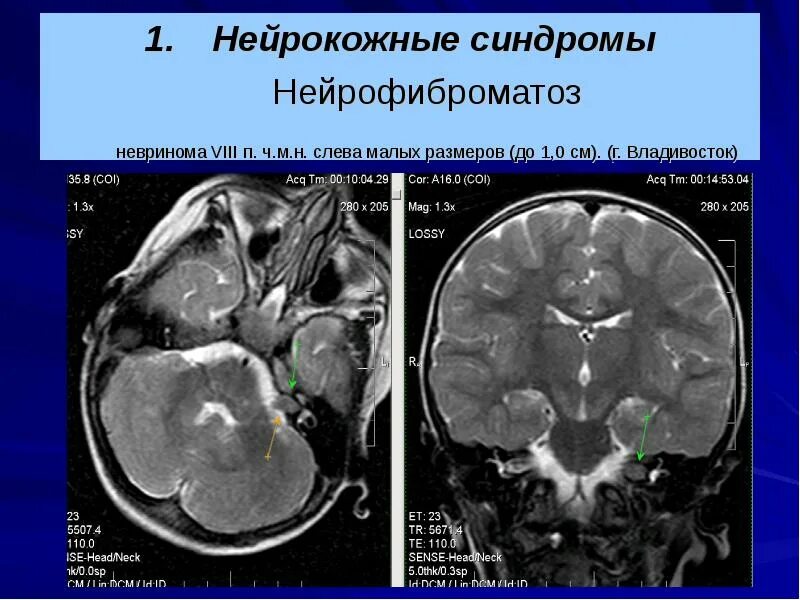

Нейрофиброматоз мрт